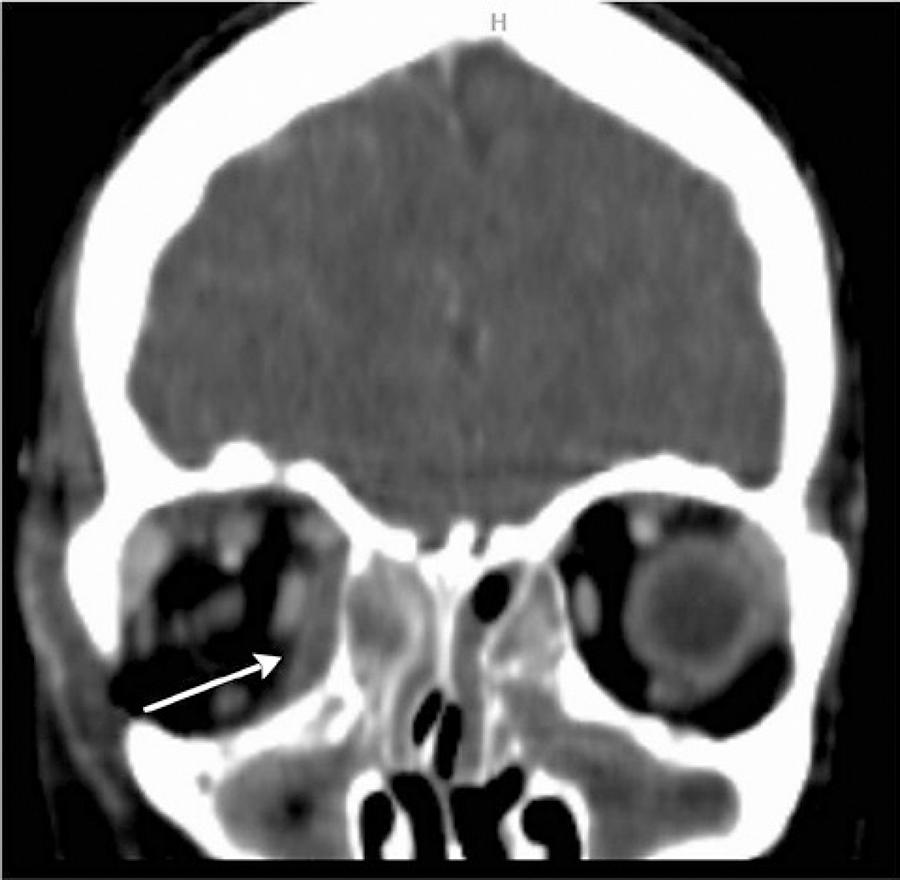

Fifty-one patients met the criteria for the study and had available medical records (29 male, 22 female). Thirty patients were treated on the otorhinolaryngology service and twenty-one patients were treated on the opthalmology service. The age range was 1 to 63 years (mean, 19.92 ± 17.98). Approximately 70% patients (n=36) were younger than 18 years of age. Thirty-two (62.7%) were diagnosed with preseptal cellulitis and 19 (37.3%) were diagnosed with postseptal cellulitis. After detailed evaluations, 15 were diagnosed with a subperiosteal abscess (SPA) and 4 with orbital cellulitis. No one had an intraorbital abscess or a cavernous sinus thrombosis. The age and gender was similar for the two groups. SPA was localized as medial (n=8) (Figure 1), superiomedial (n=4) (Figure 2), inferior (n=1) (Figure 3), and inferiomedial (n=1) (Figure 4). In the postseptal cellulitis group, bilateral pansinusitis was found in 5, unilateral pansinusitis in 6, unilateral maxillary, ethmoid, and frontal sinusitis in 5, unilateral maxillary and ethmoid sinusitis in 2, and unilateral maxillary sinusitis in 1. In the preseptal cellulitis group, bilateral pansinusitis was present in 9, unilateral pansinusitis in 10, unilateral maxillary, ethmoid, and frontal sinusitis in 4, unilateral maxillary, ethmoid sinusitis in 5, and unilateral ethmoid sinusitis in 4 patients. Five patients with medial SPA were treated with endoscopic sinus surgery, one patient with inferior SPA was treated with external surgery, and six patients with other localizations were treated with combination of endoscopic sinus surgery and external surgery. The seasonal distribution of this pathology is shown in figure 5.